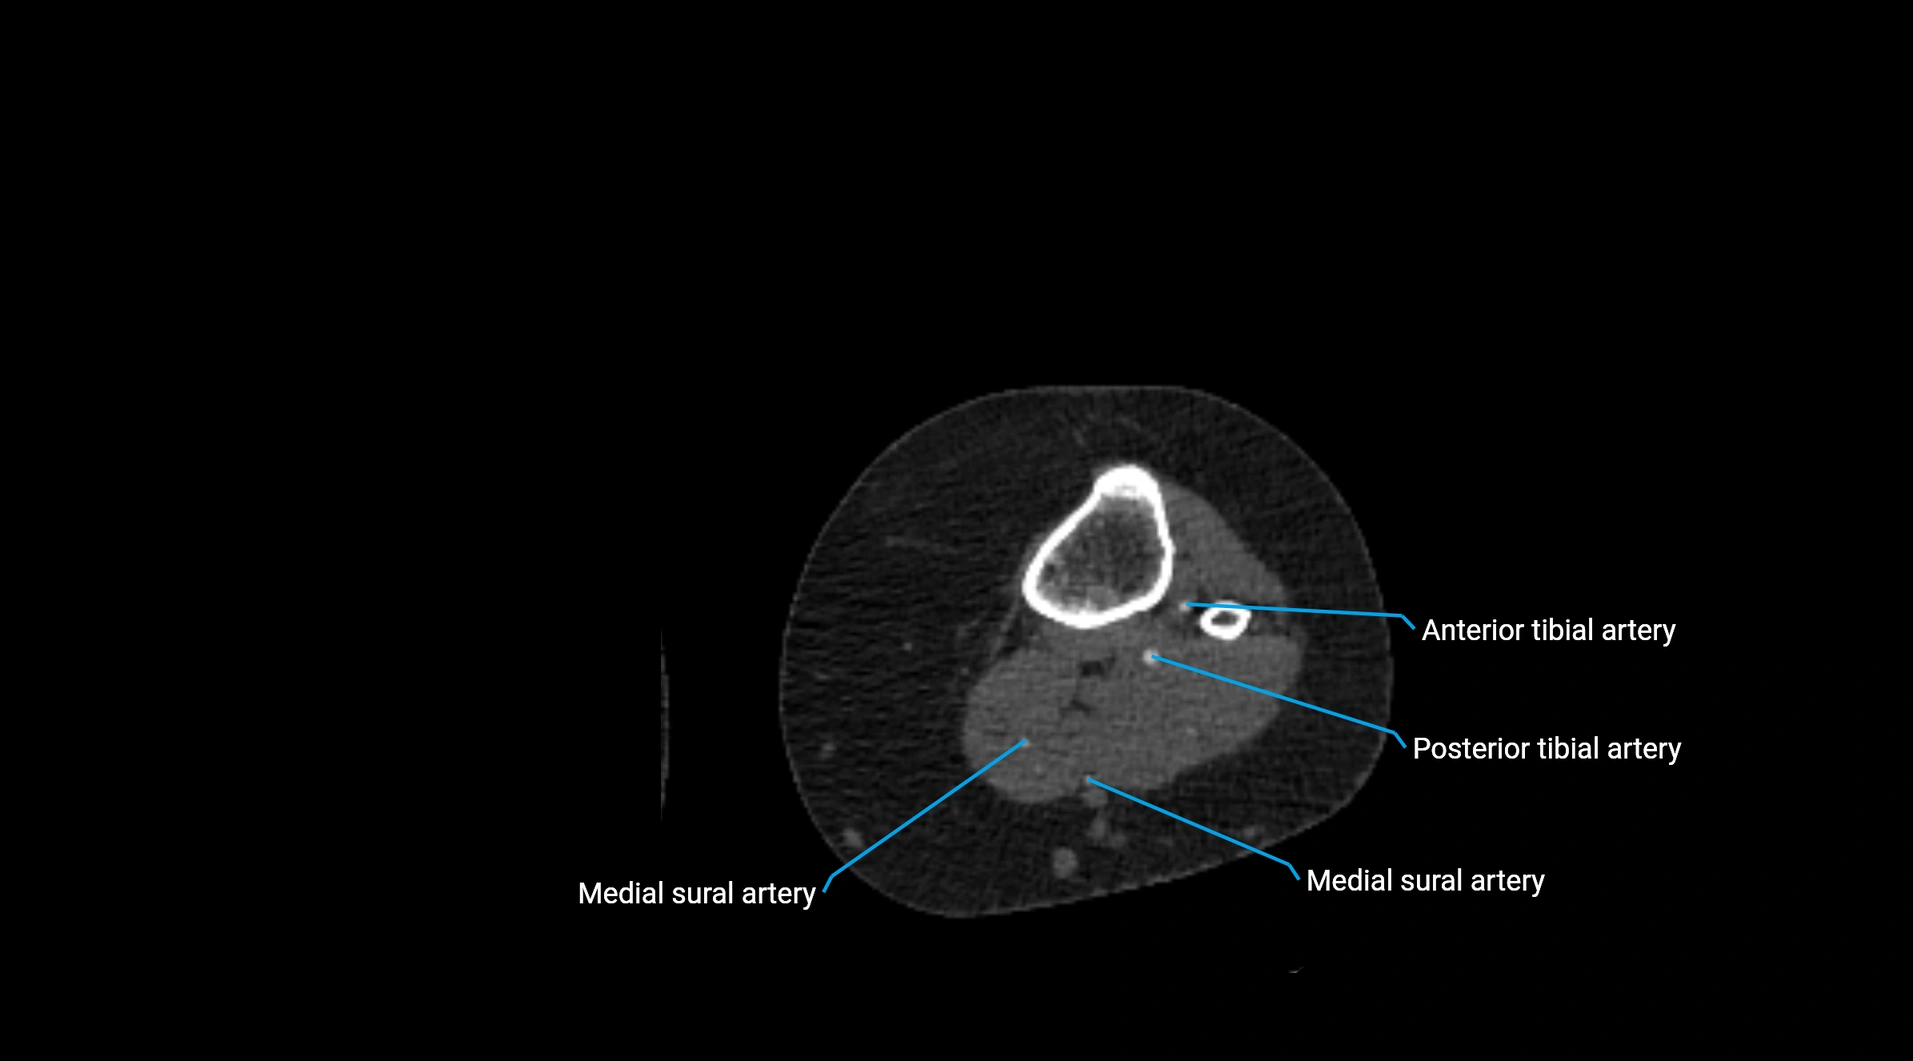

CT images

image

Contrast-enhanced CT (CTA):

• Gold standard for abdominal aortic imaging

• Provides excellent detail of lumen, wall, aneurysm, thrombus, and branch vessels

• Multiplanar and 3D reconstructions help in aneurysm measurement, stent graft planning, and dissection evaluation